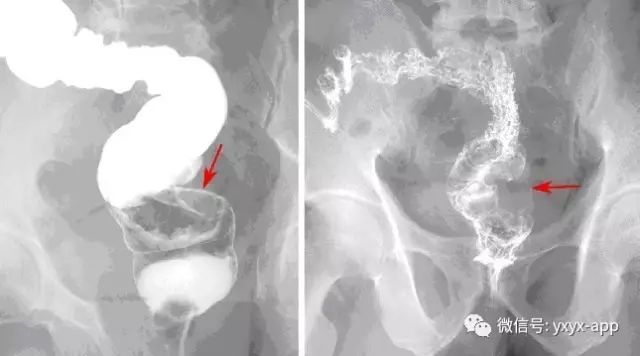

【影像表现】 钡灌肠:直肠与乙状结肠起始部可见不规则充盈缺损(图1箭头),肠管见偏心性狭窄;粘膜皱襞紊乱,纠集(图2、3箭头)。 CT:直肠壁不均匀增厚,见软组织影突入直肠腔内,增强扫描中度强化,周围脂肪间隙欠清楚,直肠后方可见肿大淋巴结(箭头)。肝脏体积增大,肝内密度欠均匀,可见多发弥漫不均匀低密度区,增强扫描病灶显示更加清楚,呈多发结节样低密度影,脾周及胆囊窝周围可见少量液性低密度影。

X线:增生型:主要表现为充盈缺损,充盈缺损周边的的粘膜破坏中断或见小溃疡。气钡双重造影可显示肿块的轮廓。溃疡型:主要表现为腔内突起的龛影和“半月征”。浸润型:主要沿肠壁环形生长,使肠壁增厚,肠腔狭窄,可见狭窄段粘膜呈锯齿状。混合型:常有两种以上的表现混合存在。

(2)病灶表现为充盈缺损 对: 错